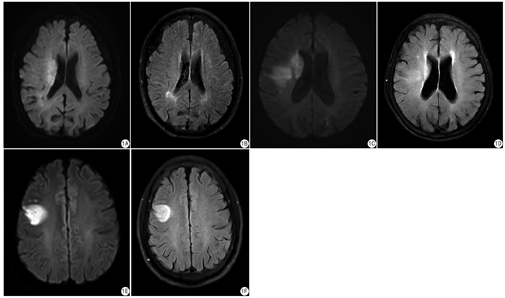

由2位有经验的神经放射学诊断医师采用双盲法对所有影像资料进行分析,结果不一致时经协商后达成一致。改良DWI-FLAIR不匹配定义为DWI高信号缺血病变区而FLAIR相同部分无高信号改变,或FLAIR信号改变区域明显小于DWI信号变化。FLAIR阴性表现为对应区域FLAIR信号无明显变化或与对侧半球信号一致。FLAIR部分阳性表现为FLAIR有信号改变,但明显小于相应的DWI病灶,且对侧FLAIR无明显信号改变。DWI梗死体积应用飞利普3.0 T MR自带的后处理工作站进行测量:在后处理工作站上对DWI图像上梗死高信号区且ADC值小于620 mm2/s区进行感兴趣区勾画,自动计算DWI梗死体积。

共100例WUIS患者纳入研究,其中64例存在改良DWI-FLAIR不匹配,36例DWI-FLAIR匹配(图1)。两组间入院NIHSS评分(14.69±7.55 vs 13.23±8.38)、入院DWI梗死体积[(23.54±15.17) mL vs (28.04±21.72) mL]大致相仿,差异无统计学意义(t=2.116,P=0.263;t=0.547,P=0.460)。改良DWI-FLAIR不匹配组[(115.84±39.75) mg/dL]入院糖化血红蛋白低于DWI-FLAIR匹配组[(124.75±48.21) mg/dL],两组间比较差异有统计学意义(t=1.049;P=0.034)(表1)。64例改良DWI-FLAIR不匹配亚组中FLARI阴性37例,FLAIR部分阳性27例(图1)。两组间入院NIHSS评分、DWI梗死体积及其他临床指标均无统计学意义(P>0.05)(表2)。